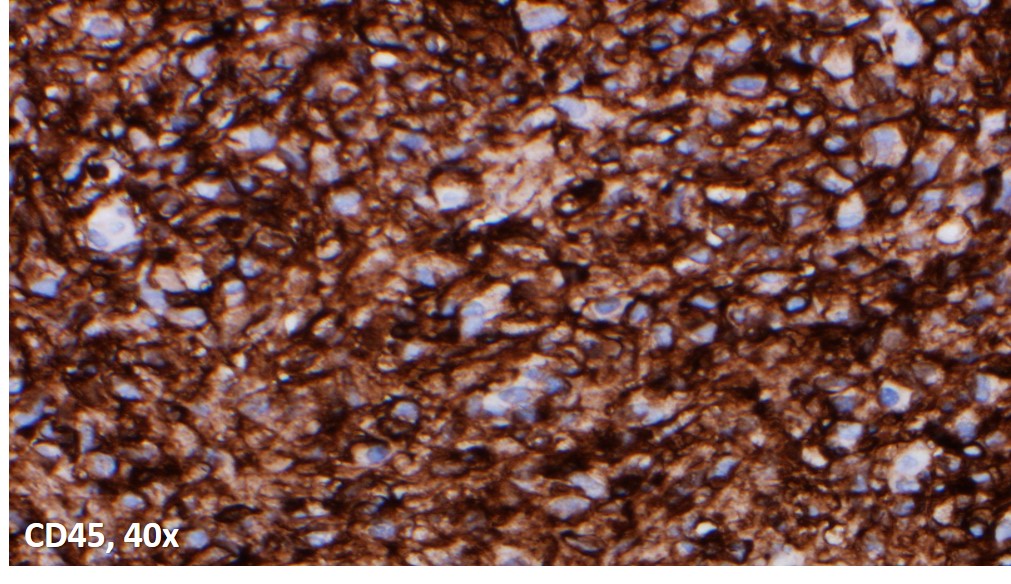

Immunoperoxidase and special stains were performed on this case. The cells were diffusely positive for CD45 and CD163, and negative for keratin cocktain, S100, CD1a and CD30. AFB and Fite were positive for acid fast bacilli, and highlighted abundant organisms. The findings were consistent with an infectious lymphadenitis, and most suggestive of a nontuberculous mycobacterial infection.